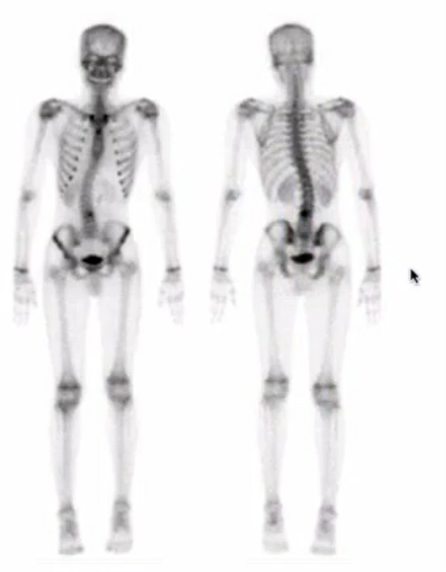

sacral insufficiency fracture